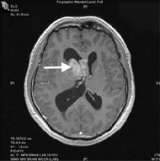

- Magnetic resonance imaging (MRI) is the preferred diagnostic tool, although the diagnosis should be confirmed by microscopic examination of the tumor from a biopsy.

- Sometimes, ependymomas are best removed with the aid of intra-operative MRI, allowing the most complete, safest surgery possible.

This post-operative MRI (above) confirms image-complete removal of the tumor. - Radiation Therapy